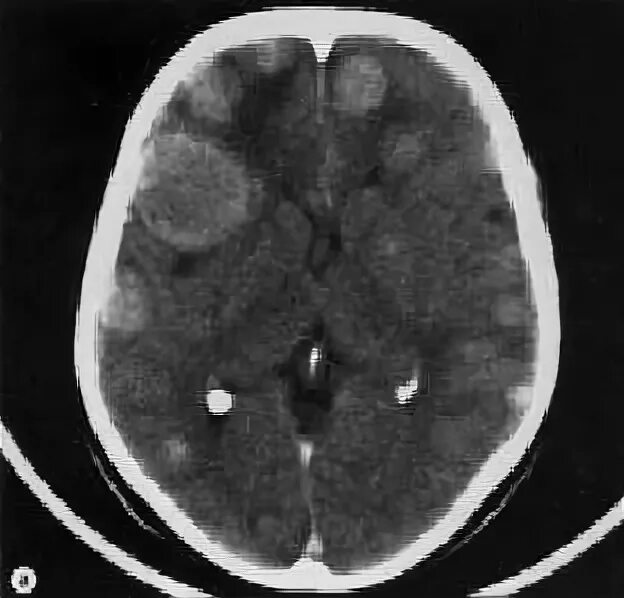

Метастазы головного мозга кт